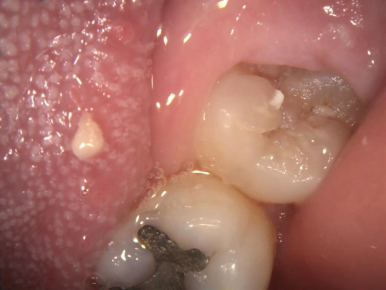

5.いつも汚れていて、口臭の原因と考えられます

左端の歯が親知らずです。ブラッシングが難しく、沢山磨き残しがあります。手前の歯も虫歯になっています。

一番奥の歯が親知らずです。汚れがたまって腫れています。